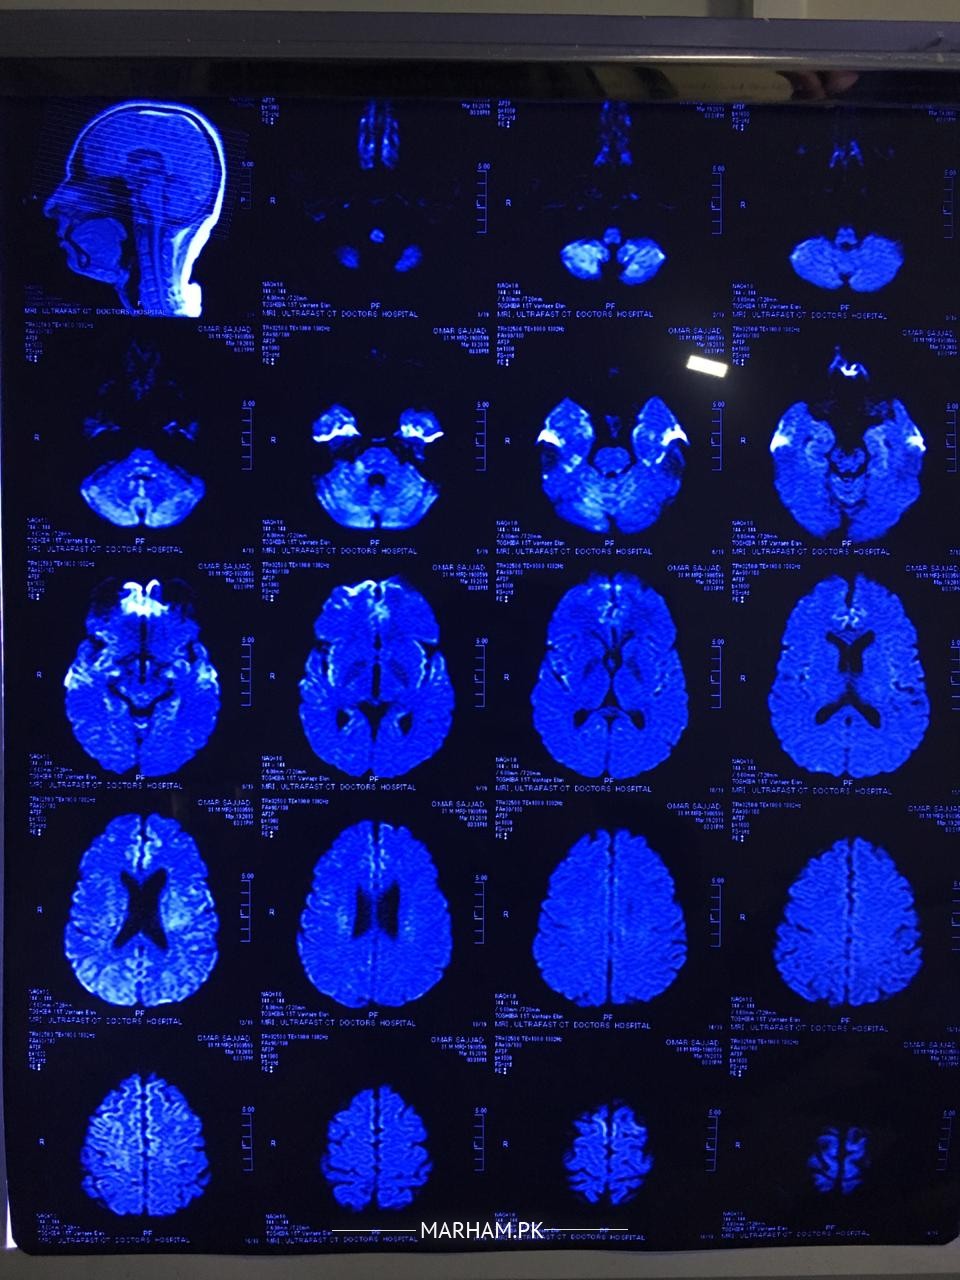

my husband had numbness in his right side of face half head. we consulted a doctor he recommended some tests and MRI. i m attaching some images plz help us understand what is the issue. m attaching all reports and images.

He is a young man and the MRI reports reveal a disease called as Multiple Sclerosis. It a disease in which body's own immune or defence system starts working against own brain tissues. It requires thorough investigations including Lumbar puncture, taking sample of fluid of brain from the spine , and few more tests. It is a chronic disease and you need to consult a neurologist so that appropriate plan of treatment can be discussed in detail.

The MRI scan report seems to suggest a diseases called Multiple Sclerosis. the dis have a deep blue tinge, therefore cannot be reliably commented upon. First the diagnosis needs to be confirmed, with contrast MRI scan and some other tests. then if it's really multiple Sclerosis then a Neurologist will discuss treatment options with you. there are good options available now to control the disease. however, I repeat , most importantly the diagnosis must be confirmed. for that you need to see a neurologist. neurological history and examination are as important as lab tests to diagnose this condition. please show a Neurologist in your city

mri brain finding are suggestive of most likely multiple sclerosis. a disease of demyelinating in nature . need detail history about your husband .